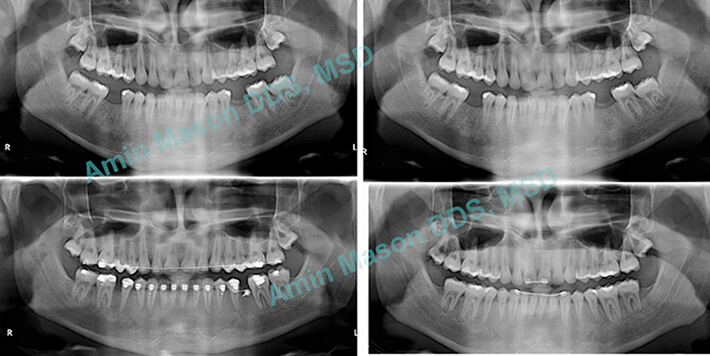

Cant Correction Case

Adult patient with a cant in maxilla (uneven gingiva) due to skeletal asymmetry. Patient did not want to have jaw surgery but wanted to improve his smile. TADS were used to mask the skeletal asymmetry.

TADs Used As Anchors

Adult patient with extraction of premolars. TADS were used instead of headgear to help with anchorage management and space closure.